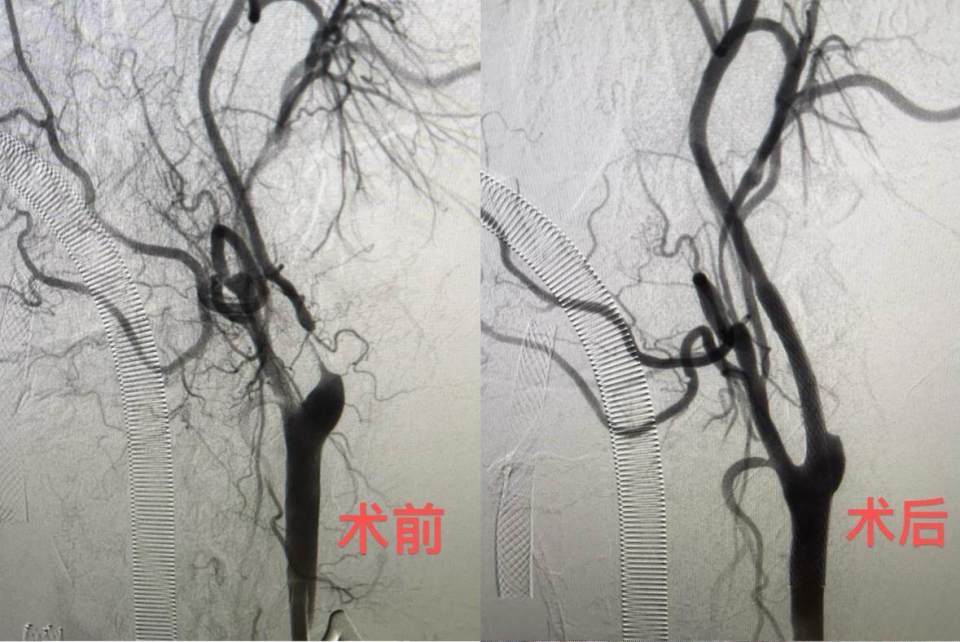

6月11日,该院神经外科陈光忠主任医师、秦琨副主任医师联合神经内科代成波主任团队,在神经电生理室、麻醉科和手术室等科室支持下,成功开展颈动脉狭窄治疗的全新术式:经颈动脉血运重建术(TCAR)。颈部开口仅2厘米,血流阻断15分钟,整个手术仅用时一小时便顺利完成。术后从影像结果可见,术前已经几乎断裂的血运通道,术后血运立即恢复。6月13日,术后2天的李大叔就已顺利出院。

图片